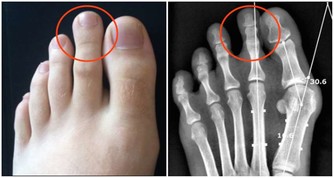

在生活中有兩種現象,一種是有人在痛風發作後,才知道自己的血尿酸水平已經遠超正常值;另一種現像是,在體檢時發現自己尿酸值高,但是,沒有什麼自覺症狀。

眾所周知,一旦尿酸高了,會引發全身性疾病,首當其衝的就是關節疾病,對於腎臟、血管等都會有不同程度的損害,還會影響血糖引發糖尿病等等。